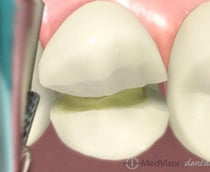

C1:

c1

歯の表面に穴が少し開いて、表層のエナメル質に限局して虫歯に犯されている状態です。まだ症状が全く出ない状態です。レジン治療が適応となります。